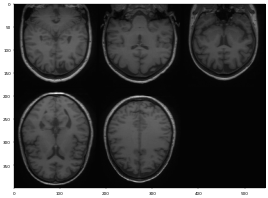

3D brain image에 대해 n4 bias field correction을 적용해보았을때의 모습이다(왼쪽 : original, 오른쪽 : processed). 자세히 살펴보면 original data에서의 low frequency를 갖는 region들이 향상이 된 부분을 볼 수 있다. (그림의 A 부분 참고)